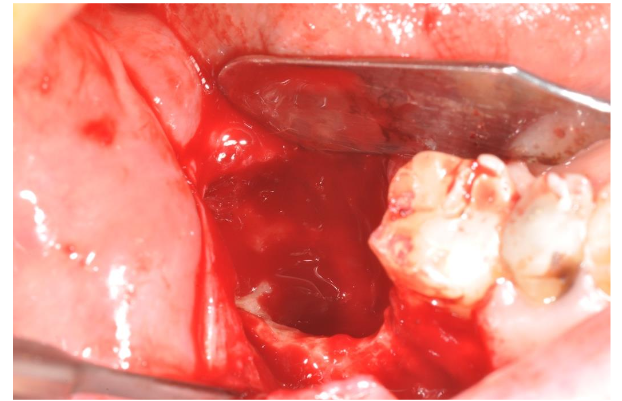

After the local anesthesia (with articain 4% with adrenaline 1:100.000, although the heart problems, but we needed a bleeding control) we opened a gingival flap removing the exophitic neoformation. The cortical bone was complete on the lingual side with a partial loss on the vestibular side: there was a big cavity that destroyed the alveolar edge behind the last residual molar (image 5). The cleaning of the upper part of the lesion made us to reach the deepest part of the bone lesion where it was possible to find granulation tissue with poor vessels and abundant necrotic bone. We completely removed these tissues with manual instrument and with ultrasonic instruments to have a total debridement of the cavity and to improve the bleeding from the residual bone walls (image 6). The necrotic bone surrounding the alveolar nerve was totally removed too.

At the end of the cleaning, the cavity was filled by PRGF®-Endoret® autologous membranes to improve the healing processes: indeed, the PRGF improves the formation of new vessels (neoangiogenesis) stimulating the cells migration and differentiation. Immediately after the PRGF application in the cavity an important bleeding appeared due to the opening of the vessels of the surrounding tissues: this is a typical phenomenon of the PRGF application (image 7). It seems that the freedom of nitric oxide from the PRGF is the cause of this bleeding for release of the smooth musculature of the vessels. However, the presence of fibrin clot autologous membranes, another product derived from the PRGF, stopped the bleeding almost immediately (image 8).